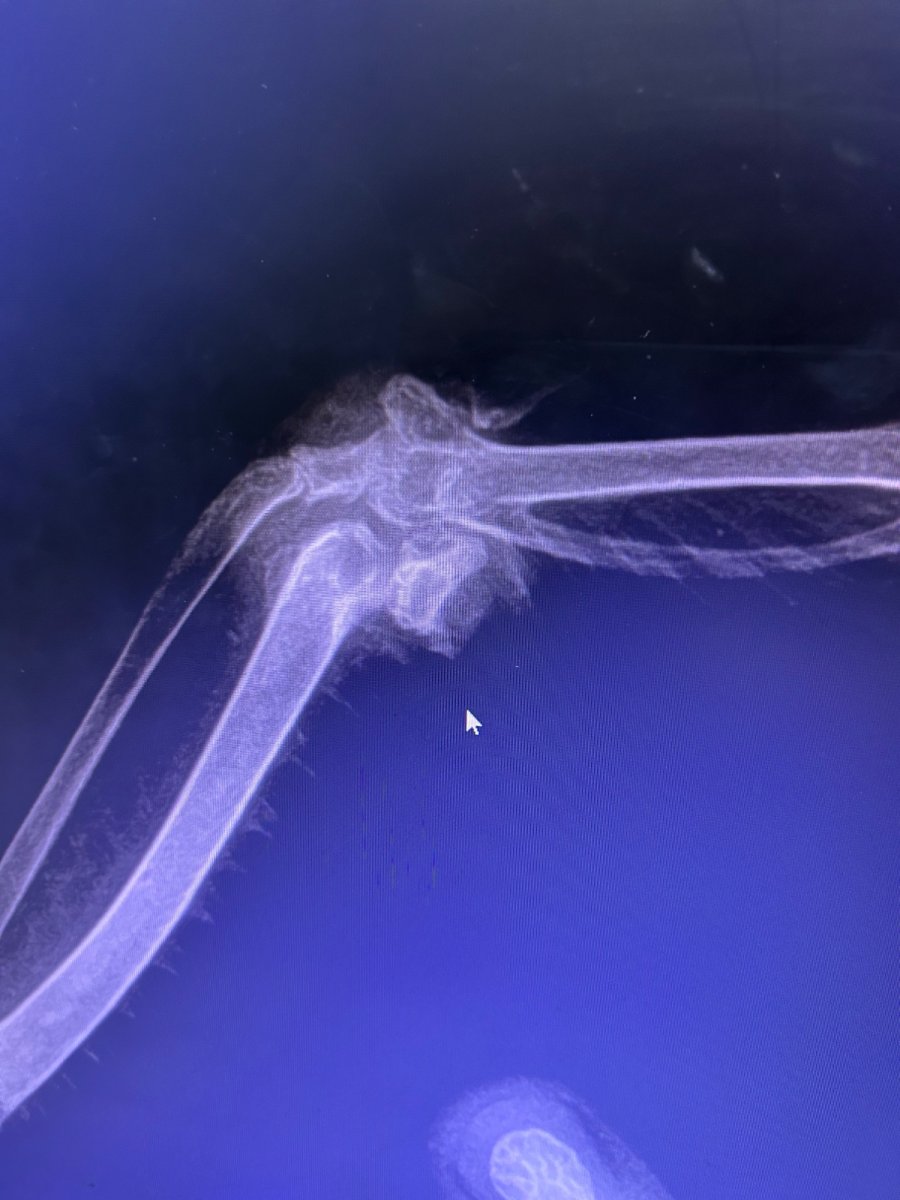

сходили к ветеринару 😀 -7,5 тыс 🤣 Хорошая новость: кости целы плохая новость: шишка на суставе недвигаемого крыла все таки есть. И причины могут быть самые разные, как нам обьяснили и артрит и оспа и от печени может идти. а еще целый пакет возможных заболеваний, которые заразны для людей и других животных. Сделали анализа на сальмонеллез и микобактериоз, по готовности скинут результаты еще у него увеличена печень и много воздуха в зобе пока прописали вот такие лекарства, почти все дома осталось, сегодня начинаем лечить. Хотя бы частично просили очень хорошо дезинфицировать, чтобы не заразиться